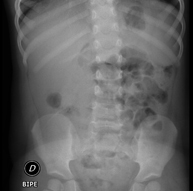

- RX Abdomen

Tècnica que usa els raigs X a través de la qual s'obtenen imatges de l'abdomen (estómac, intestí prim, intestí gros, fetge, ronyons, bufeta, pelvis òssia, etc.) per al seu estudi. - RX Columna lumbar

- Abdomen X-ray

An abdominal X-ray uses a small dose of radiation to obtain a two-dimensional image of the abdomen with its anatomical structures (stomach, small intestine, large intestine, liver, pancreas, kidneys, bladder, bony pelvis, etc.).